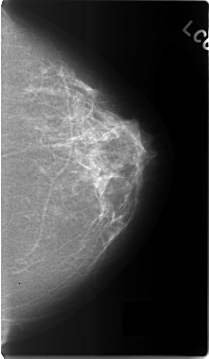

Volume: benign_04 Case: C-0302-1

C_0302_1.LEFT_MLO

C_0302_1.LEFT_CC

DENSITY 2

LEFT_MLO LINES 4592 PIXELS_PER_LINE 2736 BITS_PER_PIXEL 12 RESOLUTION 50 NON_OVERLAY

TOTAL_ABNORMALITIES 2

ABNORMALITY 1

LESION_TYPE MASS SHAPE LOBULATED MARGINS CIRCUMSCRIBED

ASSESSMENT 3

SUBTLETY 5

PATHOLOGY BENIGN

ABNORMALITY 2

LESION_TYPE CALCIFICATION TYPE PLEOMORPHIC DISTRIBUTION CLUSTERED

SUBTLETY 2